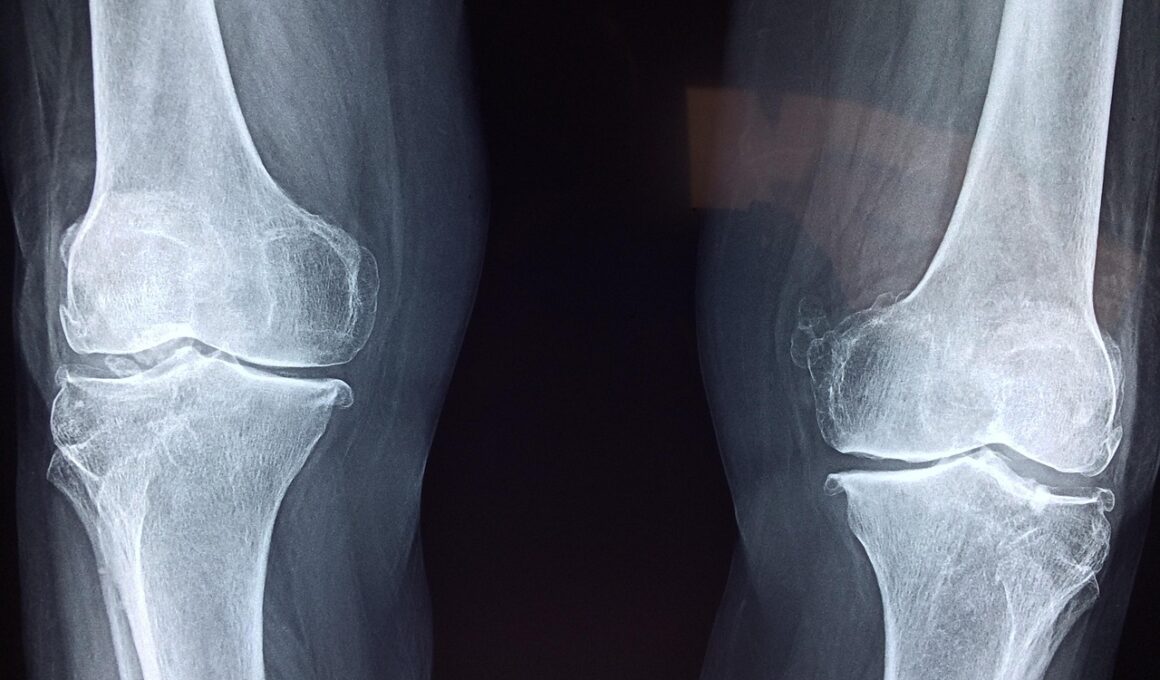

Cartilage is vital for joint health, acting as a cushion to prevent bones from rubbing against each other. Essential nutrients play a role in maintaining and regenerating cartilage, which is particularly important as we age. These nutrients can help reduce inflammation and promote cartilage synthesis, leading to improved mobility and reduced pain. Among the critical nutrients, omega-3 fatty acids stand out for their anti-inflammatory properties. These fats, found in fish oil and flaxseed, can aid in promoting joint health through their ability to inhibit inflammatory markers. Another important nutrient is glucosamine, which is often used in supplement form to help regenerate cartilage. Research suggests that glucosamine may stimulate the production of cartilage components, thereby supporting joint function. Chondroitin sulfate is also essential, often paired with glucosamine in supplements; it helps retain moisture in the joints, thus enhancing lubrication. Vitamins C and D play a role in collagen formation, crucial for cartilage strength and repair. Together, these nutrients provide a robust foundation for your joint health, significantly improving the quality of life for those suffering from joint pain or degeneration.